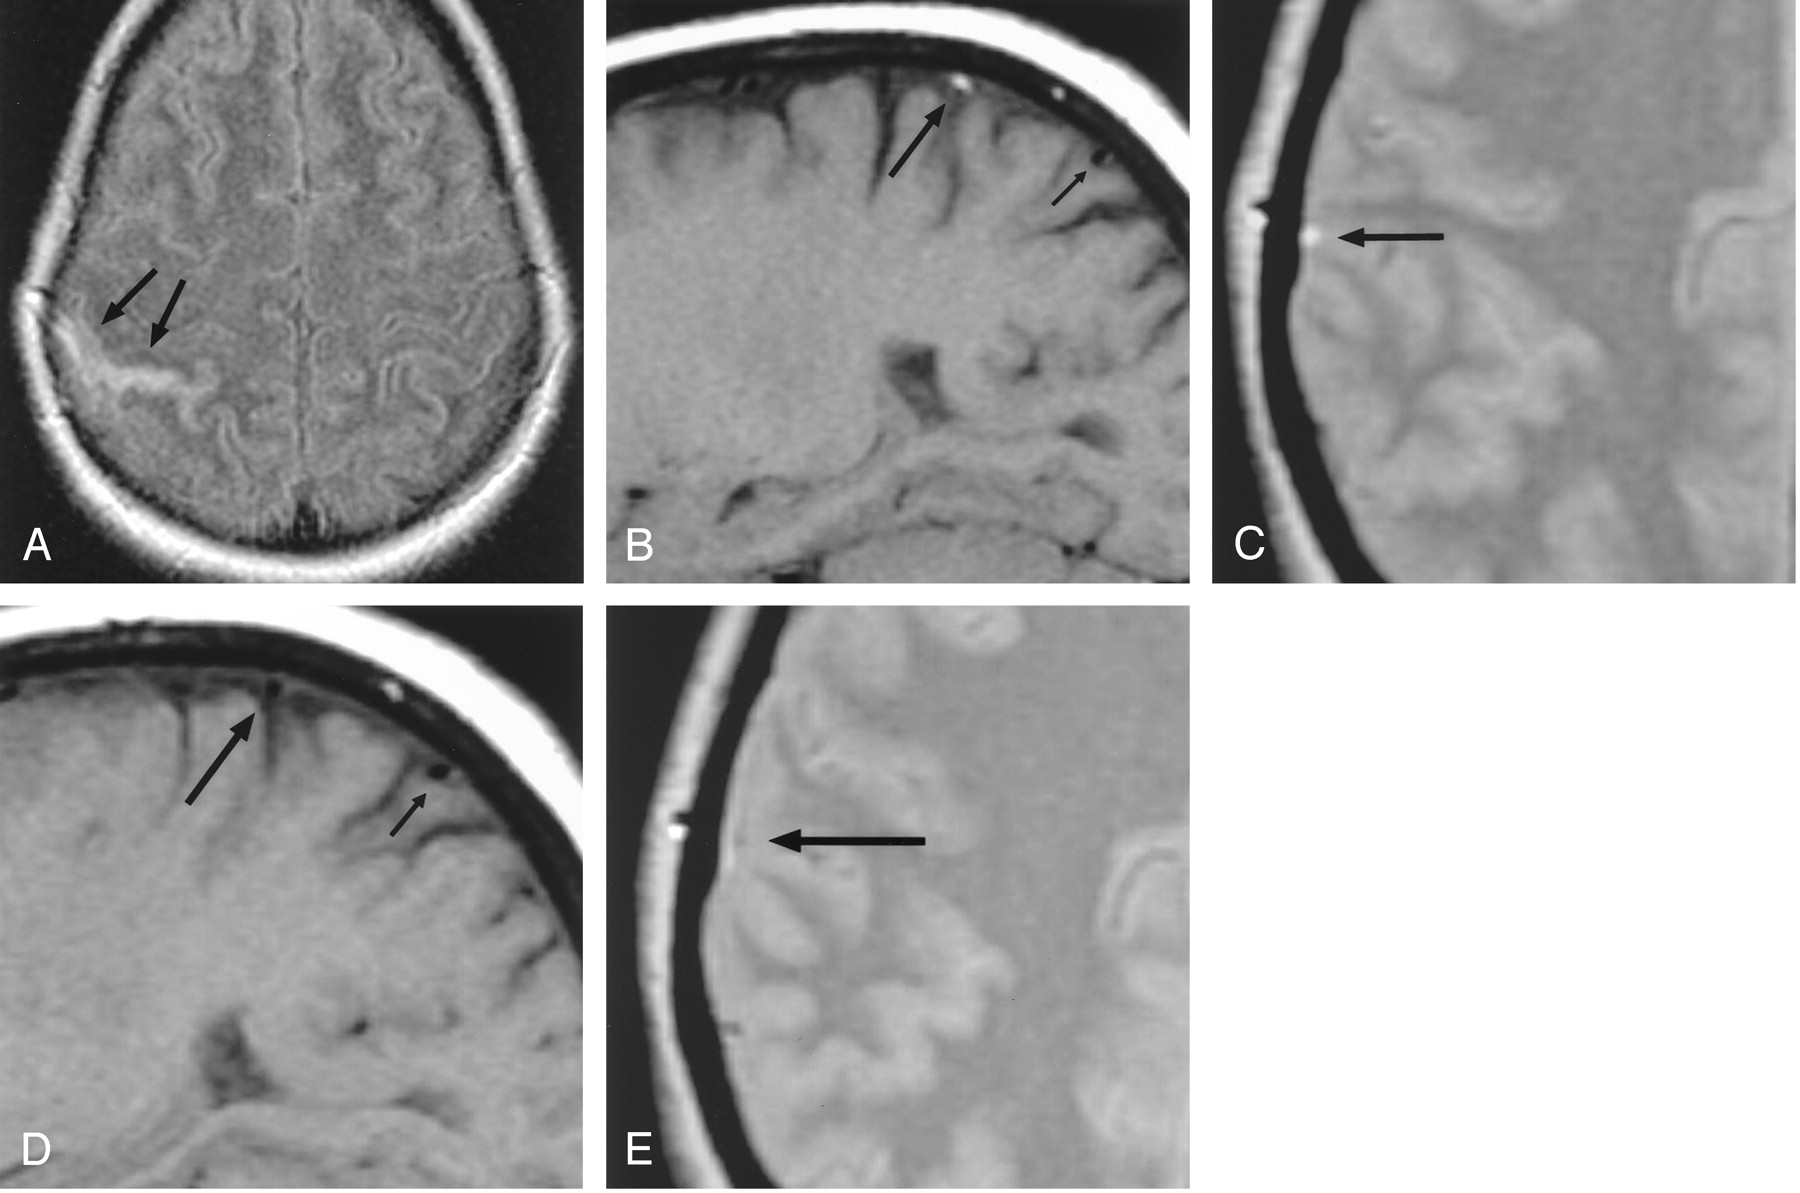

Patient 3, a 64-year-old woman with headaches and cortical venous thrombosis.

A, Axial FLAIR (10,002/158/2200) MR image shows focal sulcal hyperintensity (arrows), representing SAH, at the right frontoparietal convexity.

B, Axial CT image at the same level as the FLAIR image in panel A, obtained the following day, confirms the presence of SAH (arrow).

C, Right parasagittal T1-weighted (500/14) MR image shows luminal hyperintensity (arrow) in a right convexity cortical vein, probably the vein of Trolard; this was also identified on multiple adjacent sections.

The patient’s clinical status continued to decline. She remained febrile and septic and eventually died.